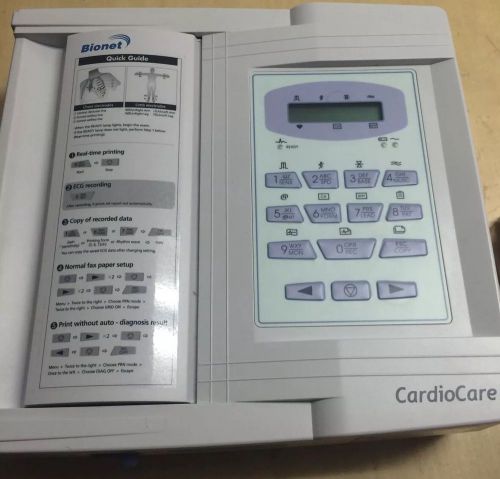

Bionet cardiocare 2000 ECG Brand NEW Affordable Interpretive ECG Machine